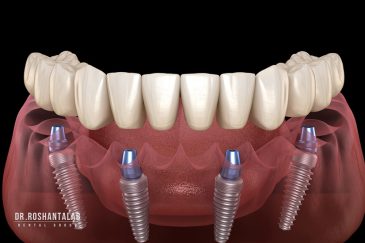

🔸 کاشت ایمپلنت دندان بدون درد

🔸کاشت ایمپلنت فلپ لس یا بدون جراحی و بدون بخیه زیر سه دقیقه

🔸 کاشت دندان یک روزه ( کشیدن و کاشت همزمان )

🔸 ایمپلنت دیجیتال و ساخت روکش دیجیتال